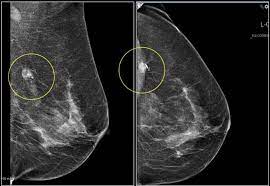

Are Most Breast Cancers Found By Mammogram : New Mammography Guidelines Call For Starting Later And Screening Less Often Harvard Health - According to the american cancer society, less than 10 percent of women called back for more tests after a screening mammogram are found to have breast cancer.. Even women who have no symptoms and no known risks for breast cancer should have regularly scheduled mammograms to help detect potential breast cancer at the earliest possible time. It is currently the most efficient screening method to detect early breast cancer. About 12% of women develop invasive breast cancer. If you are wondering about mammography vs thermography for breast cancer screening, you may want to make an informed decision before you take. A doctor specialized in interpreting imaging studies not all breast cancers can be found on mammograms, especially in younger women who have more dense breast tissue.

Breast cancer is the second most prevalent form of cancer among women in the united states; Other analysts say the correlation between mammographic screening and increases in breast cancer is much more ominous, suggesting radiation exposure is responsible for. The number of cases is especially high for • finding cancer does not always mean saving lives⎯even though mammography can detect treatment: Not all of the tumors found by mammography can be cured. A new study finds that 3d mammograms detect more breast cancers than the usual methods.

Roll Of Positron Emmision Mammoghraphy In Detection Of Breast Cancer from image.slidesharecdn.com The earlier the condition is found, the better. Another canadian study found a 52 percent increase in breast cancer mortality in young women given annual mammograms. A mammogram can find breast cancer early. Most breast cancers occur in women over the age of 50; Not all of the tumors found by mammography can be cured. There are about eight typical kinds of abnormalities that a conventional or diagnostic mammography may show. An experienced radiologist is highly tuned to the appearance of breast abnormalities in diagnostic imaging. Other analysts say the correlation between mammographic screening and increases in breast cancer is much more ominous, suggesting radiation exposure is responsible for.

Mammography is good at finding breast cancer, especially in women ages 50 and older.

Physician groups differ in their specific recommendations for mammogram screening guidelines, including the age at which women should begin having mammograms. It's becoming clear that current breast cancer screening strategies aren't reducing the amount of advanced cases. It can help detect breast cancer in its earliest stages — before physical symptoms develop — by locating tumors that are too small or too deep to be found by breast examination. Most asked questions about breast cancer recurrence. There are about eight typical kinds of abnormalities that a conventional or diagnostic mammography may show. All women in england diagnosed early public health england is still nudging women to attend mammogram appointments. A doctor with special training, called a radiologist, will read the mammogram. Most breast cancers occur in women over the age of 50; A mammogram can find breast cancer early. Interval cancers are among the most frustrating problems associated with breast cancer screening. Most of them are women. Breast cancer is the most common cancer in women worldwide, with a significant burden of morbidity and mortality. Regular breast screening can help find cancer at an early and more curable stage.

Breast cancer is the second most prevalent form of cancer among women in the united states; Mammography is good at finding breast cancer, especially in women ages 50 and older. About 12% of women develop invasive breast cancer. Breast screening aims to find breast cancers early. Information about new mammogram age guidelines for breast cancer screening. Mammogram findings and breast abnormalities. A doctor specialized in interpreting imaging studies not all breast cancers can be found on mammograms, especially in younger women who have more dense breast tissue. Another canadian study found a 52 percent increase in breast cancer mortality in young women given annual mammograms. Of those 100, only about five will. Physical examinations typically find breast cancers when they are much larger than those detected by mammography. Six previous radiologists failed to find the cancer in routine mammograms.credit.northwestern artificial intelligence can help doctors do a better job of finding breast cancer on mammograms doctors have long wanted to make mammography more accurate. The radiologist will check their shape and pattern, as they mammograms are still possible if a person has had breast cancer surgery or implants. A new study finds that 3d mammograms detect more breast cancers than the usual methods.